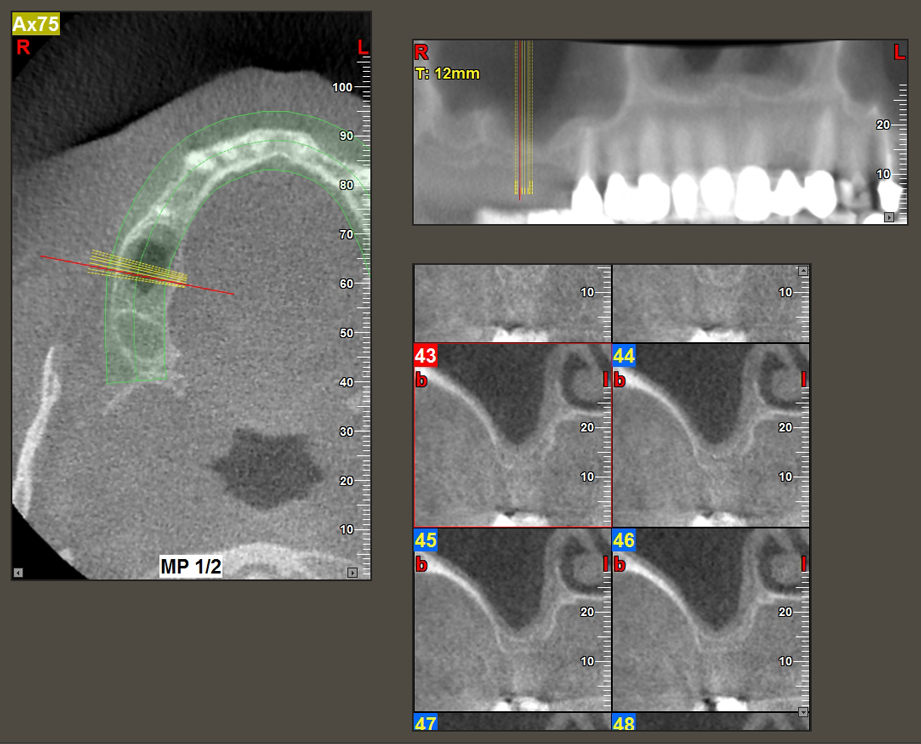

49-летняя пациентка, некурящая и не имеющая ничего примечательного в общей истории болезни, была направлена в нашу хирургическую стоматологическую клинику для хирургического удаления зуба 16 и последующей имплантации. После удаления зуба пациентка перенесла синусит в легкой форме, в результате чего мы сначала выждали шесть месяцев перед проведением операции. Остаточная высота кости при запланированном положении имплантата составляла 3-4 мм (рис. 1 и 2).

После промежуточного контроля (рис. 4) был проведен еще один этап подготовки (рис. 5). За тем, с помощью гидравлического инструмента Z35P мембрана была поднята в нужное положение (рис. 6 и 7). Далее, следовала дальнейшая пьезохирургическая подготовка ложа для имплантата, завершенная с помощью ротационного бора и лопаточной фрезы до диаметра имплантата 4,8 мм. Перед установкой имплантата под мембрану Шнейдера был введен аугментационный материал (размер частиц около 0,8-1,6 мм) (рис. 8).

Для перемещения аугментационного материала в направлении верхнечелюстной пазухи атравматично, имплантат вводился очень медленно вручную (рис. 9). При этом мембрана еще раз выталкивалась в краниальном направлении. Через два месяца место операции зажило без раздражения. Через шесть месяцев рентгеновский контроль показал значительное увеличение помутнения, что свидетельствует об оссификации (рис. 10). Протезирование было проведено металлокерамической коронкой.